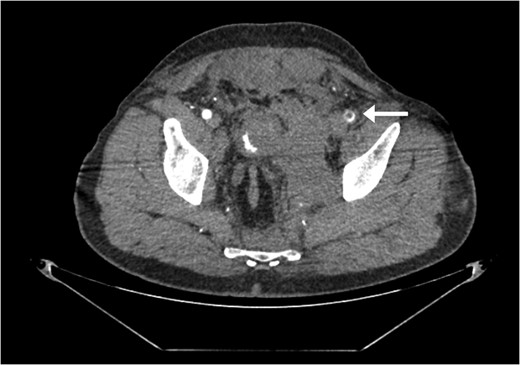

A 55-year-old male arrived at the ER, a large tree having fallen across his pelvis. The patient was hypotensive at the scene. He received over 1500 ml of crystalloid in route to the emergency room. Upon arrival to St. Mary’s Medical Center, the patient had a systolic pressure of 70. His heart rate was in the 130 s. The patient was awake and alert. A left subclavian central line was placed and he was transfused with two units of O-blood. The patient’s abdomen was soft and nontender. The patient had blood at his meatus. The patient’s pelvis was tender to palpation. His left leg was cold, mottled and pulseless. There was no femoral pulse on the left side. The chest x-ray was normal, however, the pelvis film revealed extreme widening and displacement of the symphysis pubis (Fig. 1). A bedsheet was wrapped around the patient’s pelvis and another two units of O-packed red blood cells were administered. Additionally, he was given four units of fresh frozen plasma. The patient was started on norepinephrine to control his persistent hypotension. His systolic blood pressure rose into the mid-90s and the patient was taken to the CT scanner. The CT scan revealed that the patient had an acute occlusion of his left iliac artery, as well as a large left iliac wing fracture with a massive associated hematoma. A right iliac wing fracture was located near the sacroiliac joint. There was pubic diastasis, as well as a left superior rami fracture with a modest associated hematoma. There was no extravasation of dye (Figs 2 and 3). The patient was taken directly to the operating room because he was developing significant abdominal distention in the face of continued hypotension. Anesthesiologists placed a second large-bore central line for fluid resuscitation. An exploratory laparotomy was performed, revealing an intraperitoneal bladder rupture. The patient was bleeding freely from his pelvic hematoma. Multiple attempts were made to pack the pelvis tightly with laparotomy pads, but efforts were unsuccessful. Because of the distorted anatomy obtaining proximal and distal control of the iliacs was extremely difficult. The patient suffered massive retroperitoneal venous bleeding, which we were unable to control. The patient exsanguinated on the operating room table; despite having received over 30 units of packed red blood cells, 30 units of fresh frozen plasma, several 10 packs of platelets, cryoprecipitate and factor VII A.

Large retroperitoneal hematoma. Arrow depicts injured left iliac artery.